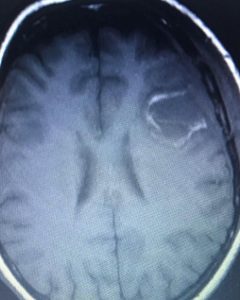

Local anesthesia is one of the oldest forms of anesthesia and is adequate for opening the skull to remove a tumor. A patient with a tumor in the left frontal or temporal region such as this young lady that I operated upon recently can be monitored for their speech function while the tumor is removed under local anesthesia.